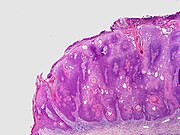

Inverted follicular keratosis[notes 1] Asymptomatic, firm, white–tan to pink papules[14] Microscopically it is characterized as a well-circumscribed inverted acanthotic squamous proliferation containing squamous eddies and without significant atypia.[17] SkinTumors-P6190325.JPG